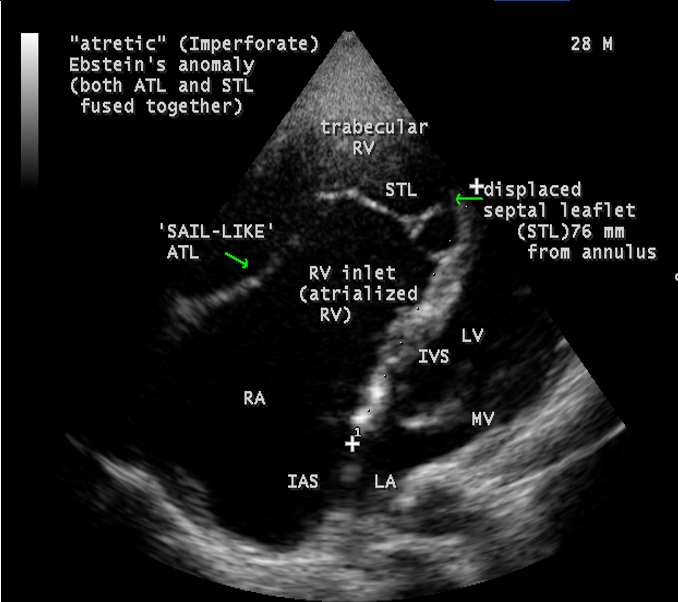

A 28-year old male presented with cyanosis and auscultation revealed a ‘sail sound’ ( loud tricuspid component of first heart sound due to increased tension developed by the large anterior leaflet as it reaches the limits of its systolic excursion- an important sign of anterior leaflet mobility), a ‘cadence’ quality of quadruple rhythm due to wide splitting of first and second sounds ( due to complete right bundle branch block), atrial and ventricular filling sounds (summation of these sounds due to prolonged PR interval). ECG revealed the features of Ebstein’s anomaly as shown in Figures 11 and 12. X-ray chest revealed the Ebstein’s configuration as shown in Figure 13. 2D echocardiography revealed a ‘sail-like’anterior tricuspid leaflet forming a ‘muscular curtain’ in between the inflow and trabecular parts of the right ventricle as an ‘imperforate membrane’ with a ‘pinhole’communication, associated with a muscular VSD (ventricular septal defect) in the proximal, atrialized compartment of right ventricle suggesting an ‘atretic” (‘imperforate’) Ebstein’s anomaly as shown in Figures 14 to 27.

Echocardiographic features Echocardiography is the diagnostic test of choice for Ebstein’s anomaly and the first echocardiographic diagnosis was reported by Lundstrom in 1969. The first diagnostic criteria for Ebstein’s anomaly using a multi-crystal two-dimensional system was defined by Hagan in 1974 [33] and they were able to recognize the apical displacement of the septal tricuspid leaflet and an elongated anterior tricuspid leaflet with increased excursion. The septal leaflet of the tricuspid valve attaches chiefly to the ventricular septum , but part of its basal attachment is to the posterior wall of the right ventricle [34] and it normally exhibits a slight but distinct apical displacement of its basal attachment to the central fibrous body compared to the mitral valve. The distal displacement of septal origin of tricuspid valve seems to be the best echocardiographic criterion as the characteristic sign for Ebstein’s anomaly and the degree of maximal displacement in normal hearts varies considerably with a mean difference of approximately 6 mm with mitral valve. To define the anatomic severity of Ebstein’s anomaly, four-chamber view is the best to demonstrate the apical displacement of septal tricuspid leaflet [35]. The ratio between the mitral-to-apex distance and the tricuspid-to-apex distance varies from 1 to 1.2 in normal subjects and 1.8 to 3.2 in patients and it is 3.6 as in Figure 18 with Ebstein’s anomaly. The true distance in the level of insertion of atrioventricular valves is obtained by substracting the tricuspid-to-apex distance from the mitral-to-apex distance with a mean value of 27.25 ± 12 mm in patients with proven Ebstein’s anomaly and it is 60 mm as shown in Figure 18 compared to reference group (5.7 ± 2 mm). Kambe and coworkers calculated the distance between both atrioventricular valves directly as a mean value of 21 mm with a range of 14 to 32 mm [36]. A maximum difference in the level of valve insertion of >15 mm in children and >20 mm in adults is discriminated between normal and Ebstein’s anomaly [37],[38]. Despite this fact, a patient with an ‘unequivocal’ Ebstein’s malformation can be encountered in whom the diagnosis cannot be made with certainity solely on the basis of apical displacement of the septal tricuspid valve leaflet. Occasionally, the leaflet attaches to the trabecular part rather than the inlet part of the septum, the conventional four-chamber view will not reveal any septal insertion as shown in Figures 28 and 29.

The anterior tricuspid leaflet is not involved in the process of downward displacement, it may be abnormally inserted occasionally and Shiina, et al documented the apical displacement of anterior tricuspid leaflet in 14% of cases echocardiographically [39]. The anterior leaflet forms a large, sail-like intracavitary curtain as in Figures 14, 25 and contains muscular strands instead of consisting entirely of a fibrous membrane as in the normal tricuspid valve [40]. It is potentially mobile with a brisk sail-like movement as shown in Figure 21 to 24 [41], free bloating with a ‘whipping motion’ across the right ventricular outflow tract (RVOT) as shown in Figure 26 and in some cases, the movement is restricted due to its adherence to the ventricular wall as in Figure 1 and 2, 4 and 9. It is often fenestrated, may in part be musculaized , inserting into the trabeculations of the right ventricle (RV) as in Figure 28 and rarely, the anterior leaflet forms an ‘atretic’ membrane that spans the midportion of the right ventricular cavity as in Figure 16.

Ebstein’s original case was an example of obstruction at the tricuspid orifice by a membrane dividing the right ventricle into two halves as shown in Figure 16 of a 28-year old cyanotic male with ECG and X-ray characteristics as in Figure 11 to 13. suggesting an advanced spectrum of Ebstein’s malformation , necessitating RV exclusion techniques such as Starnes’ procedure. The florid case of Ebstein’s anomaly with the insertion of leaflet tissue along with ventricular walls as a ‘blanket’ as in Figures 28 and 29 in a 30-year old cyanotic male may go for an initial palliation with bidirectional Glenn shunt (cavopulmonary anastomosis). The other variants of moderate degree of leaflet tethering with varying degrees of regurgitation, but an intact basal leaflet attachments with atrioventricular junction as in Cases 1 and 2 may need a definite repair. In Ebstein’s mitral valve as in Figure 32 in a 10-year old boy, the downward displacement of functional annulus > 0.8 cm/m2 is not particularly striking and tends to affect the septal leaflet (anterior mitral leaflet) alone. The valve is thickened and mildly regurgitant due to rheumatic involvement rather than an anatomic cause.